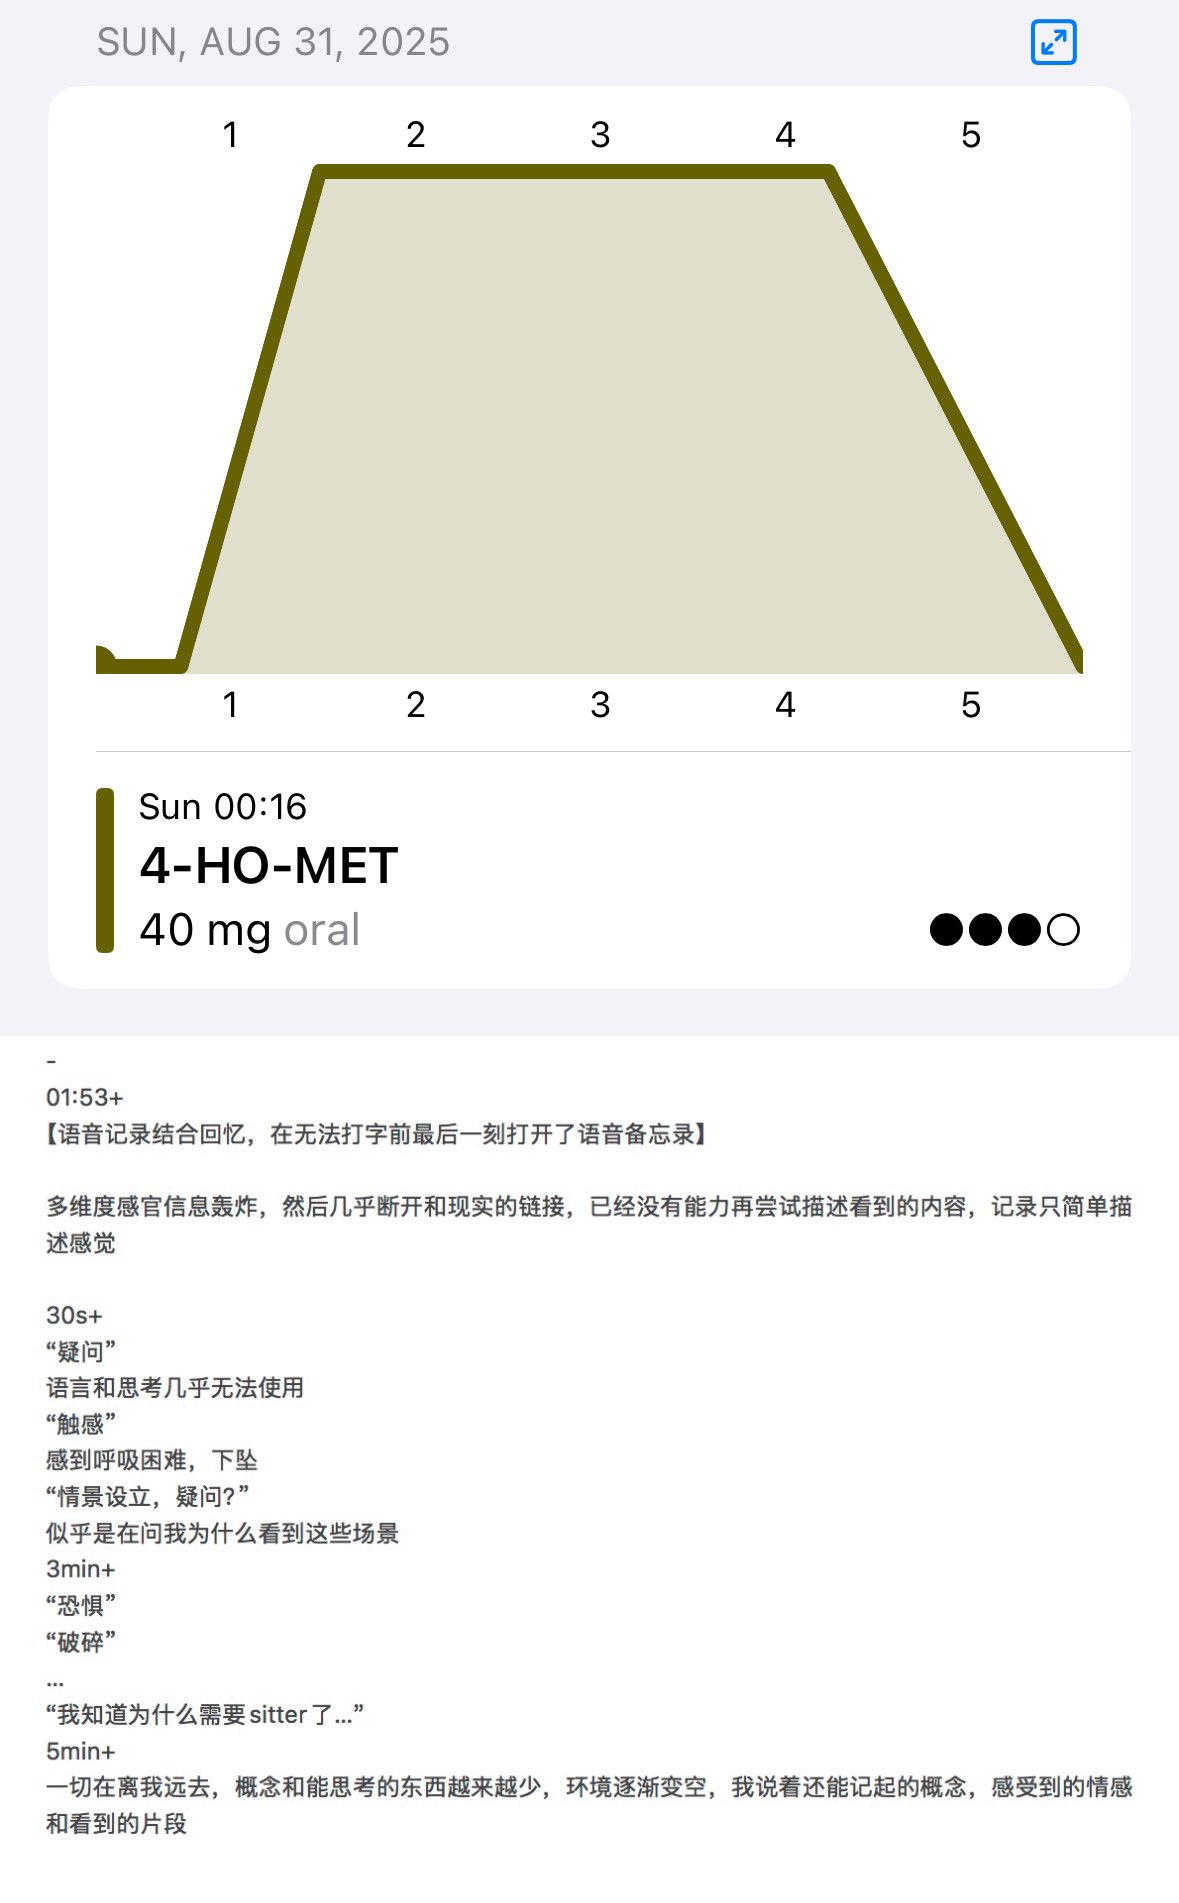

今天起来特别晕,完全不知道是怎么回事,以为是昨天测试物质的副作用我在想这么恐怖,然后怀疑今天是不是丁螺环酮吃了两次,直到我去看用药记录。。

好家伙唑吡坦又骗我吃药了还顺带上了个失忆状态,这下子知道是谁干的了。吃auv之后dxm清除得特别慢...让我感觉要从此告别了的程度,加上我基因检测本来cyp2d6就是中速代谢,这个尾巴就被拖的特别长

炽烈已极 @AnIncandescence醒了躺在床上的时候想着怎么还有内幻呢,像是在拉摇杆操纵游戏里的小人,以一个俯瞰的视角(经典)

炽烈已极 @AnIncandescence迷迷糊糊的平白无故很开心,想着原来冬天睡觉这么舒服的吗在被子里蛄蛹()后来真相大白是刷出欣快tag了,robo就是比较容易出